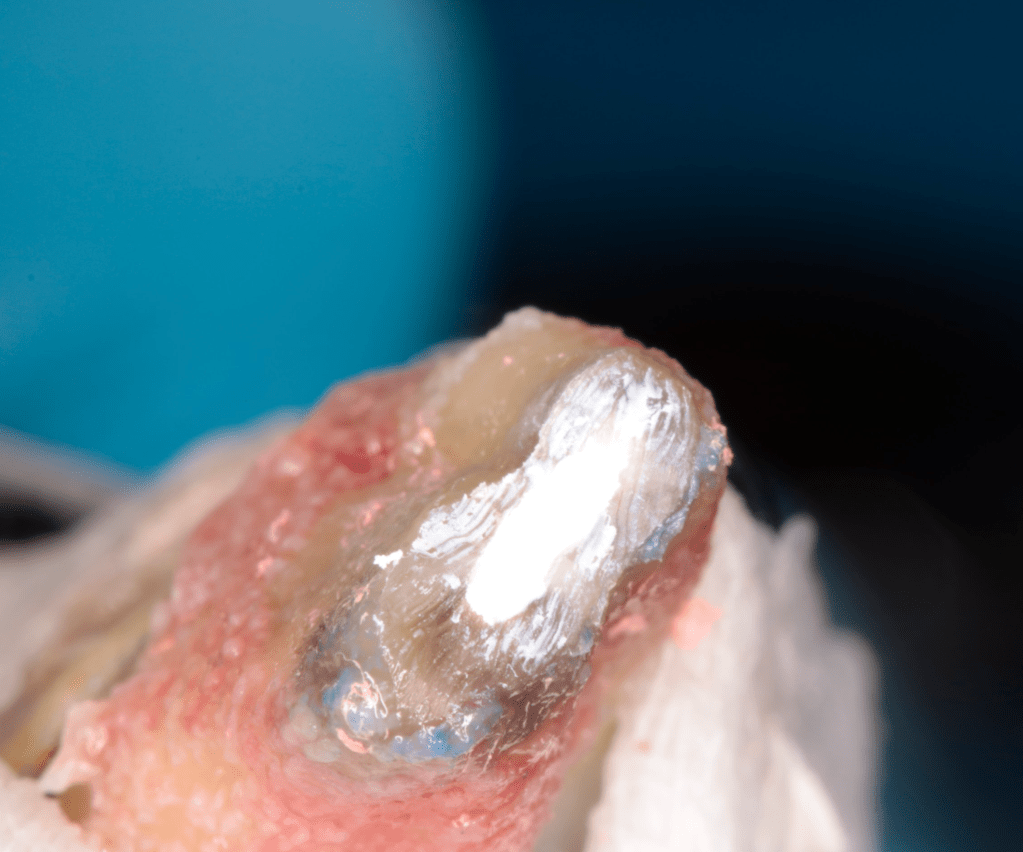

Reconstrucción preendodóntica

Reco pared vesticular